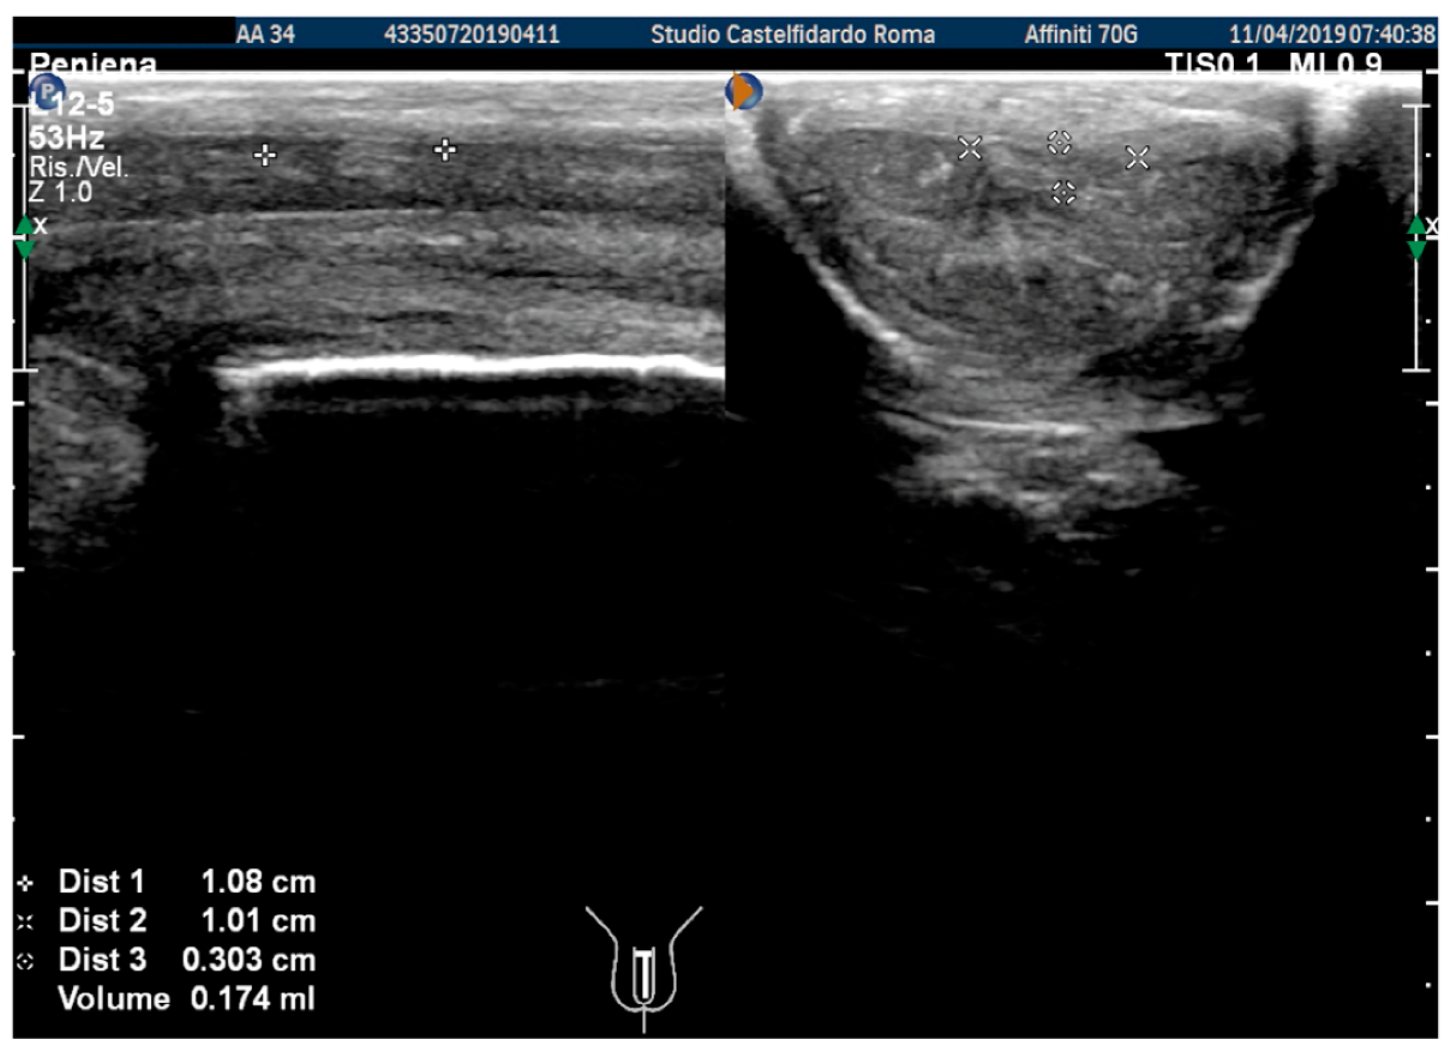

| 1 | 34 years | Congenital lateral-left penile curvature (10-degrees) | Middle third | (A) 10.8 × 10.1 × 3.03 mm volume = 174 mm3 | (A) 40-degree left curvature | (A) score 2 | (A) score 26 | 2 years and 5 months | orally: Silymarin 400 mg + Ginkgo biloba 250 mg + Propolis 600 mg + Bilberry 160 mg + Vitamin E 800 IU/once a day, for 29 months. + topically: Propolis creme/twice a day/for 29 months. * The patient refused peri-plaque penile injections |

| (B) No plaque detected | (B) 10-degree left penile curvature (previous condition = congenital lateral left penile curvature) | (B) score 0 (after 12 months) | (B) score 26 | ||||||